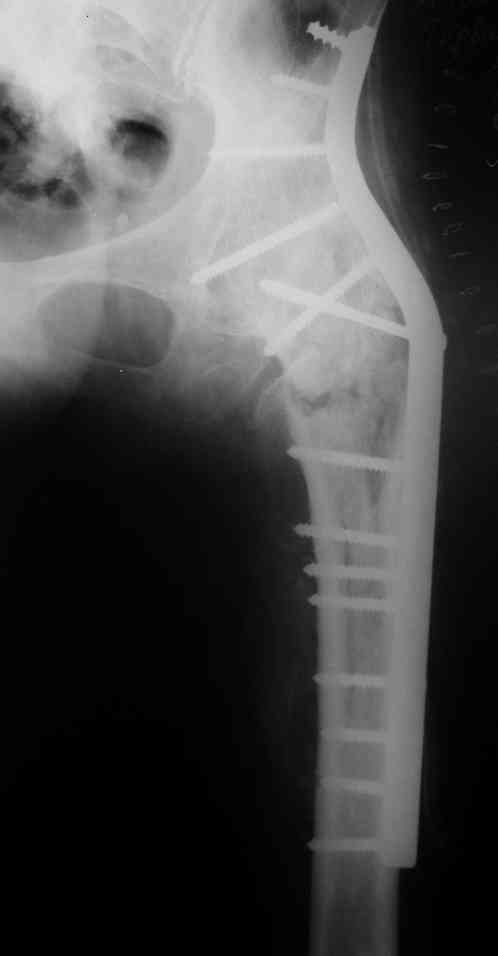

Рентгенограммы до и после. Больной профессор на кафедре сопромата и после детального изучения

особенностей имплантата, собственных рентгенограмм дал добро на операцию. Ваш вариант лечения вполне симпатичен.

С уважением А.Семенистый.